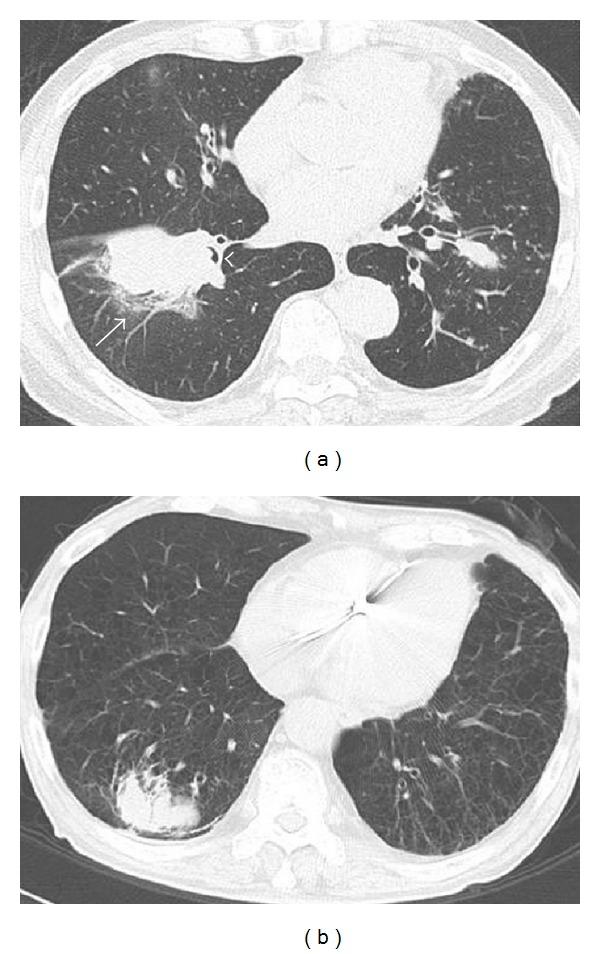

Recent agents, that is, pemetrexed and bevacizumab, have shown reproductive negative association between squamous histology. According to these agents' effectiveness, ruling out of the squamous histology is a significant issue for surgical pathologists. Several articles have proposed the distinction of peripheral type from central type of squamous cell carcinoma (SqCC) due to its similarity to adenocarcinoma, although little evidence to support the difference between these two types was published. In this study, we compared the clinicopathologic findings of central and peripheral pulmonary SqCCs.

15 central and 35 peripheral types of SqCC from 2005 to 2010 were examined. Twelve morphological features were scored based on their intensity in the original H&E slides, and then, tissue microarray holding triplicated cores from 43 cases was immunohistochemically examined for cytokeratin (CK)7, CK14, TTF-1, Napsin A, p63, CK34 β E12, CK5/6, and p53.

Most of the histological findings did not separate central and peripheral SqCCs; only the presence of emphysema, interstitial fibrosis, and entrapped pneumocytes inside the tumor showed statistic predominance in peripheral SqCC. This is the first immunophenotypic research in the central and peripheral types of SqCC.